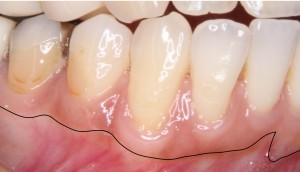

※歯肉・歯槽粘膜境

歯ぐきの境界(歯肉歯槽粘膜境)について

上の写真で黒い線を引いている部分は、**歯肉歯槽粘膜境(しにくしそうねんまくきょう)**と呼ばれる場所です。

ここは、歯ぐきの性質が変わる境界線のような部分になります。

この線より

-

上(歯のある側)

→ **角化歯肉(かくかしにく)**と呼ばれる、比較的しっかりとした歯ぐき -

下(唇や頬の側)

→ **可動粘膜(かどうねんまく)**と呼ばれる、動きやすく柔らかい粘膜

となっています。

根面被覆術では、この角化歯肉の量が治療の結果に関係することが知られています。

一般的に、歯ぐきの退縮がこの境界線を越えてしまい、角化歯肉がほとんどない状態になると、治療の難易度が高くなる場合があります。

今回の症例の歯ぐきの状態

今回の患者様の場合は、歯ぐきの退縮は確認されましたが、歯肉歯槽粘膜境を越えてしまうほどの退縮ではありませんでした。

また、最も歯ぐきの下がりが大きかった右下の犬歯の部分でも、診査の結果、約2mm程度の角化歯肉が残っている状態と判断しました。

このように、角化歯肉が一定量残っている場合は、治療計画を立てるうえで重要な参考になります。